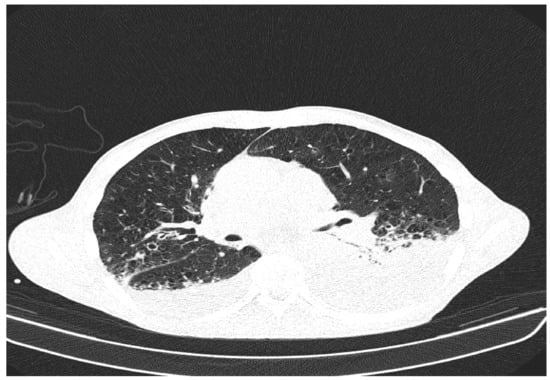

• Bilateral mediastinal, laterotracheal lymphadenopathy (maximum axial diameter: 13 mm on the right side and 11 mm on the left side), right hilar (maximum 13 mm), and infrared (maximum 18 mm);

• Bilateral posterobasal pleurisy (liquid blade with a thickness of 40 mm on the right side and 41 mm on the left side) (Figure 5).

Figure 5. Patient’s computer tomography: bilateral posterior-basal pleurisy.